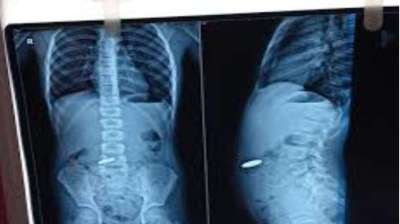

बच्चे ने मुंह में डाले सिक्के, सांस अटकने लगी; मेडिकल टीम की सतर्कता से टली बड़ी अनहोनी

दिल्ली : दिल्ली के एक सरकारी अस्पताल के डॉक्टरों ने 12 वर्षीय बच्चे की जान बचाई है। बच्चे ने पांच और दस रुपये के तीन सिक्के निगल लिए थे। सिक्के...